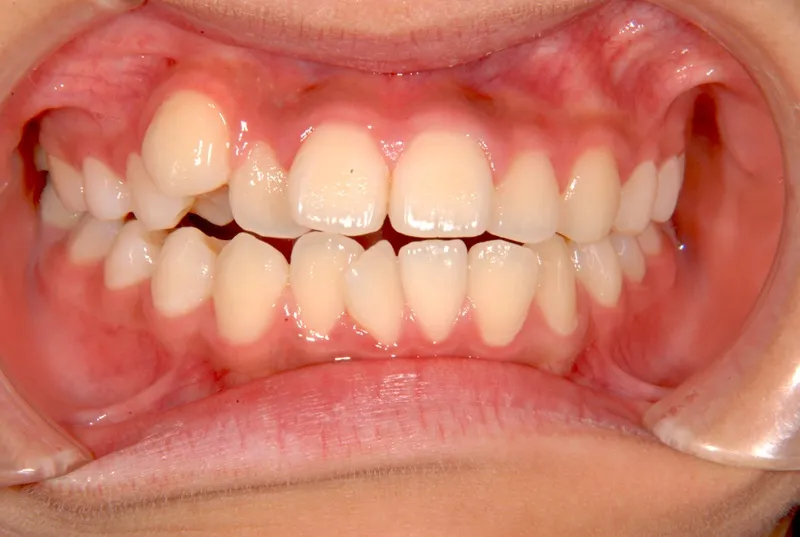

初診時年齢 中学生 (女性) 主訴 八重歯・噛めない

診断名 叢生・開咬 装置名

状態 ガタガタ・でこぼこに生えている(叢生)

八重歯(叢生)

前歯で噛めない(開咬/オープンバイト)

歯ががたがたで、噛み合わせもずれています。